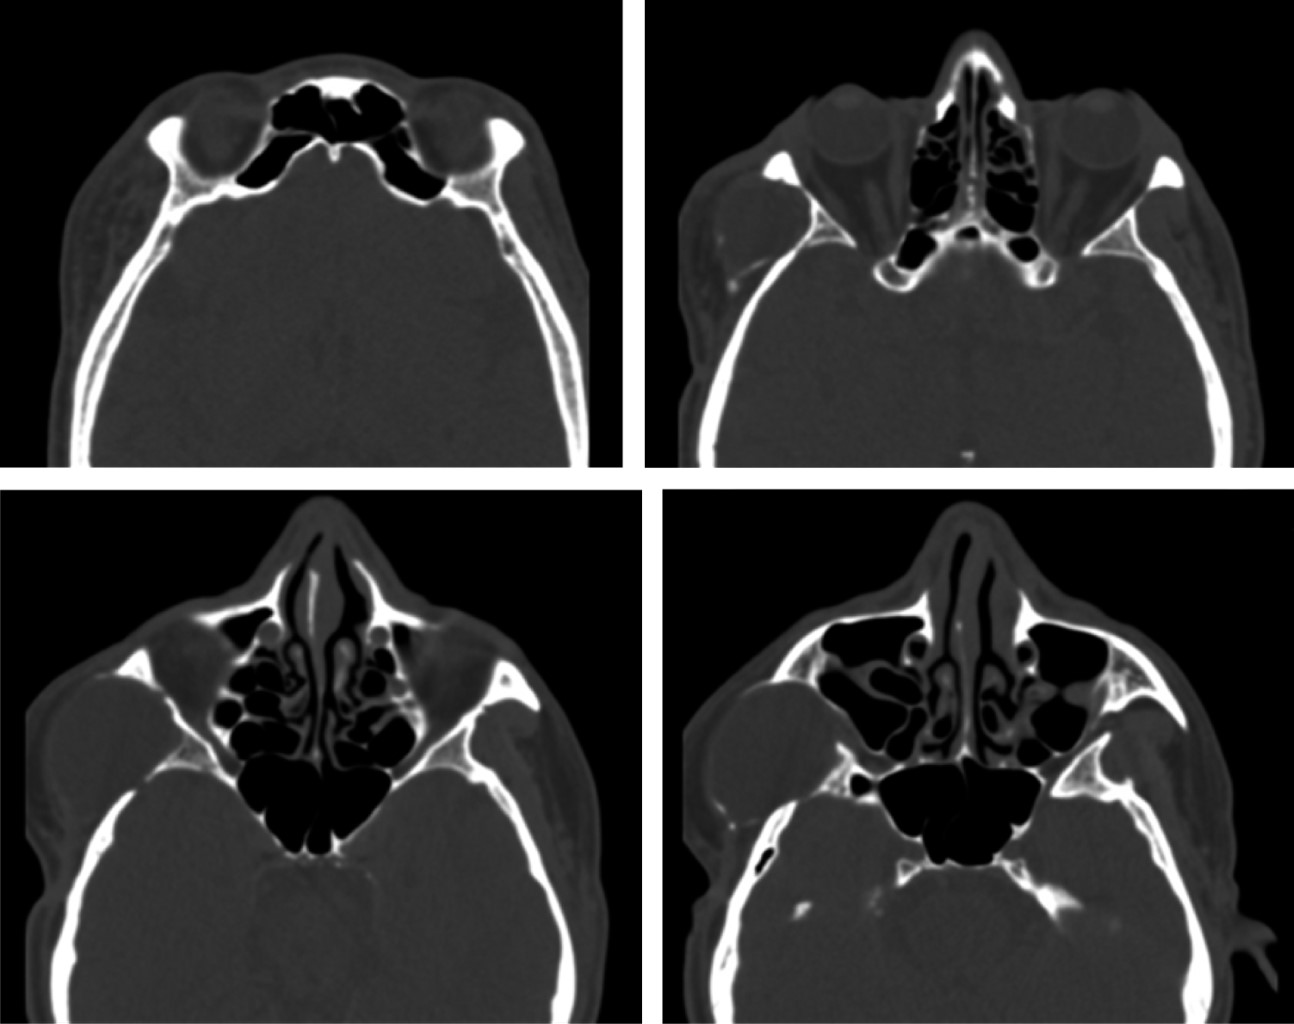

Se evaluó una tomografía computarizada (TC) de cabeza, una imagen isodensa en región de fosa temporal derecha, en la cual se observa infiltrando músculo temporal, extendiéndose a región de ATM derecha. Causando erosión de cortical del arco cigomático (Figura 2). Donde se evidencia imagen hiperdensa la cual se extiende imitando el contorno mandibular derecho hasta región de parasínfisis mandibular izquierda. Compatible con material de osteosíntesis de reconstrucción mandibular por el defecto óseo postresección de cuerpo, para sínfisis y rama mandibular derecha (Figura 3).

Figura 2